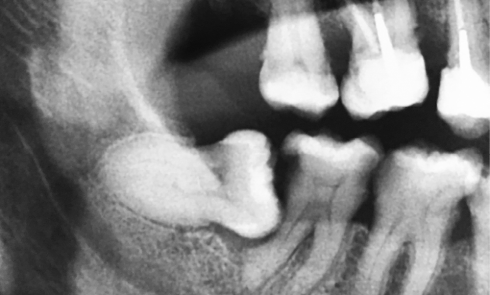

Article réservé à nos abonnés Conserver ou extraire les dents de sagesse : le point sur les indications et les techniques chirurgicales

L’extraction des troisièmes molaires est une intervention fréquente en chirurgie orale qui représente environ 36 % des actes d’extraction. Prendre la...